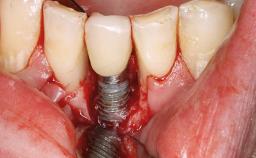

Peripheral Giant-cell Granuloma Associated with Peri-implant Tissues

# of Implants 5

Type of Implants One-Piece

Placement Protocol Early or late implant placement